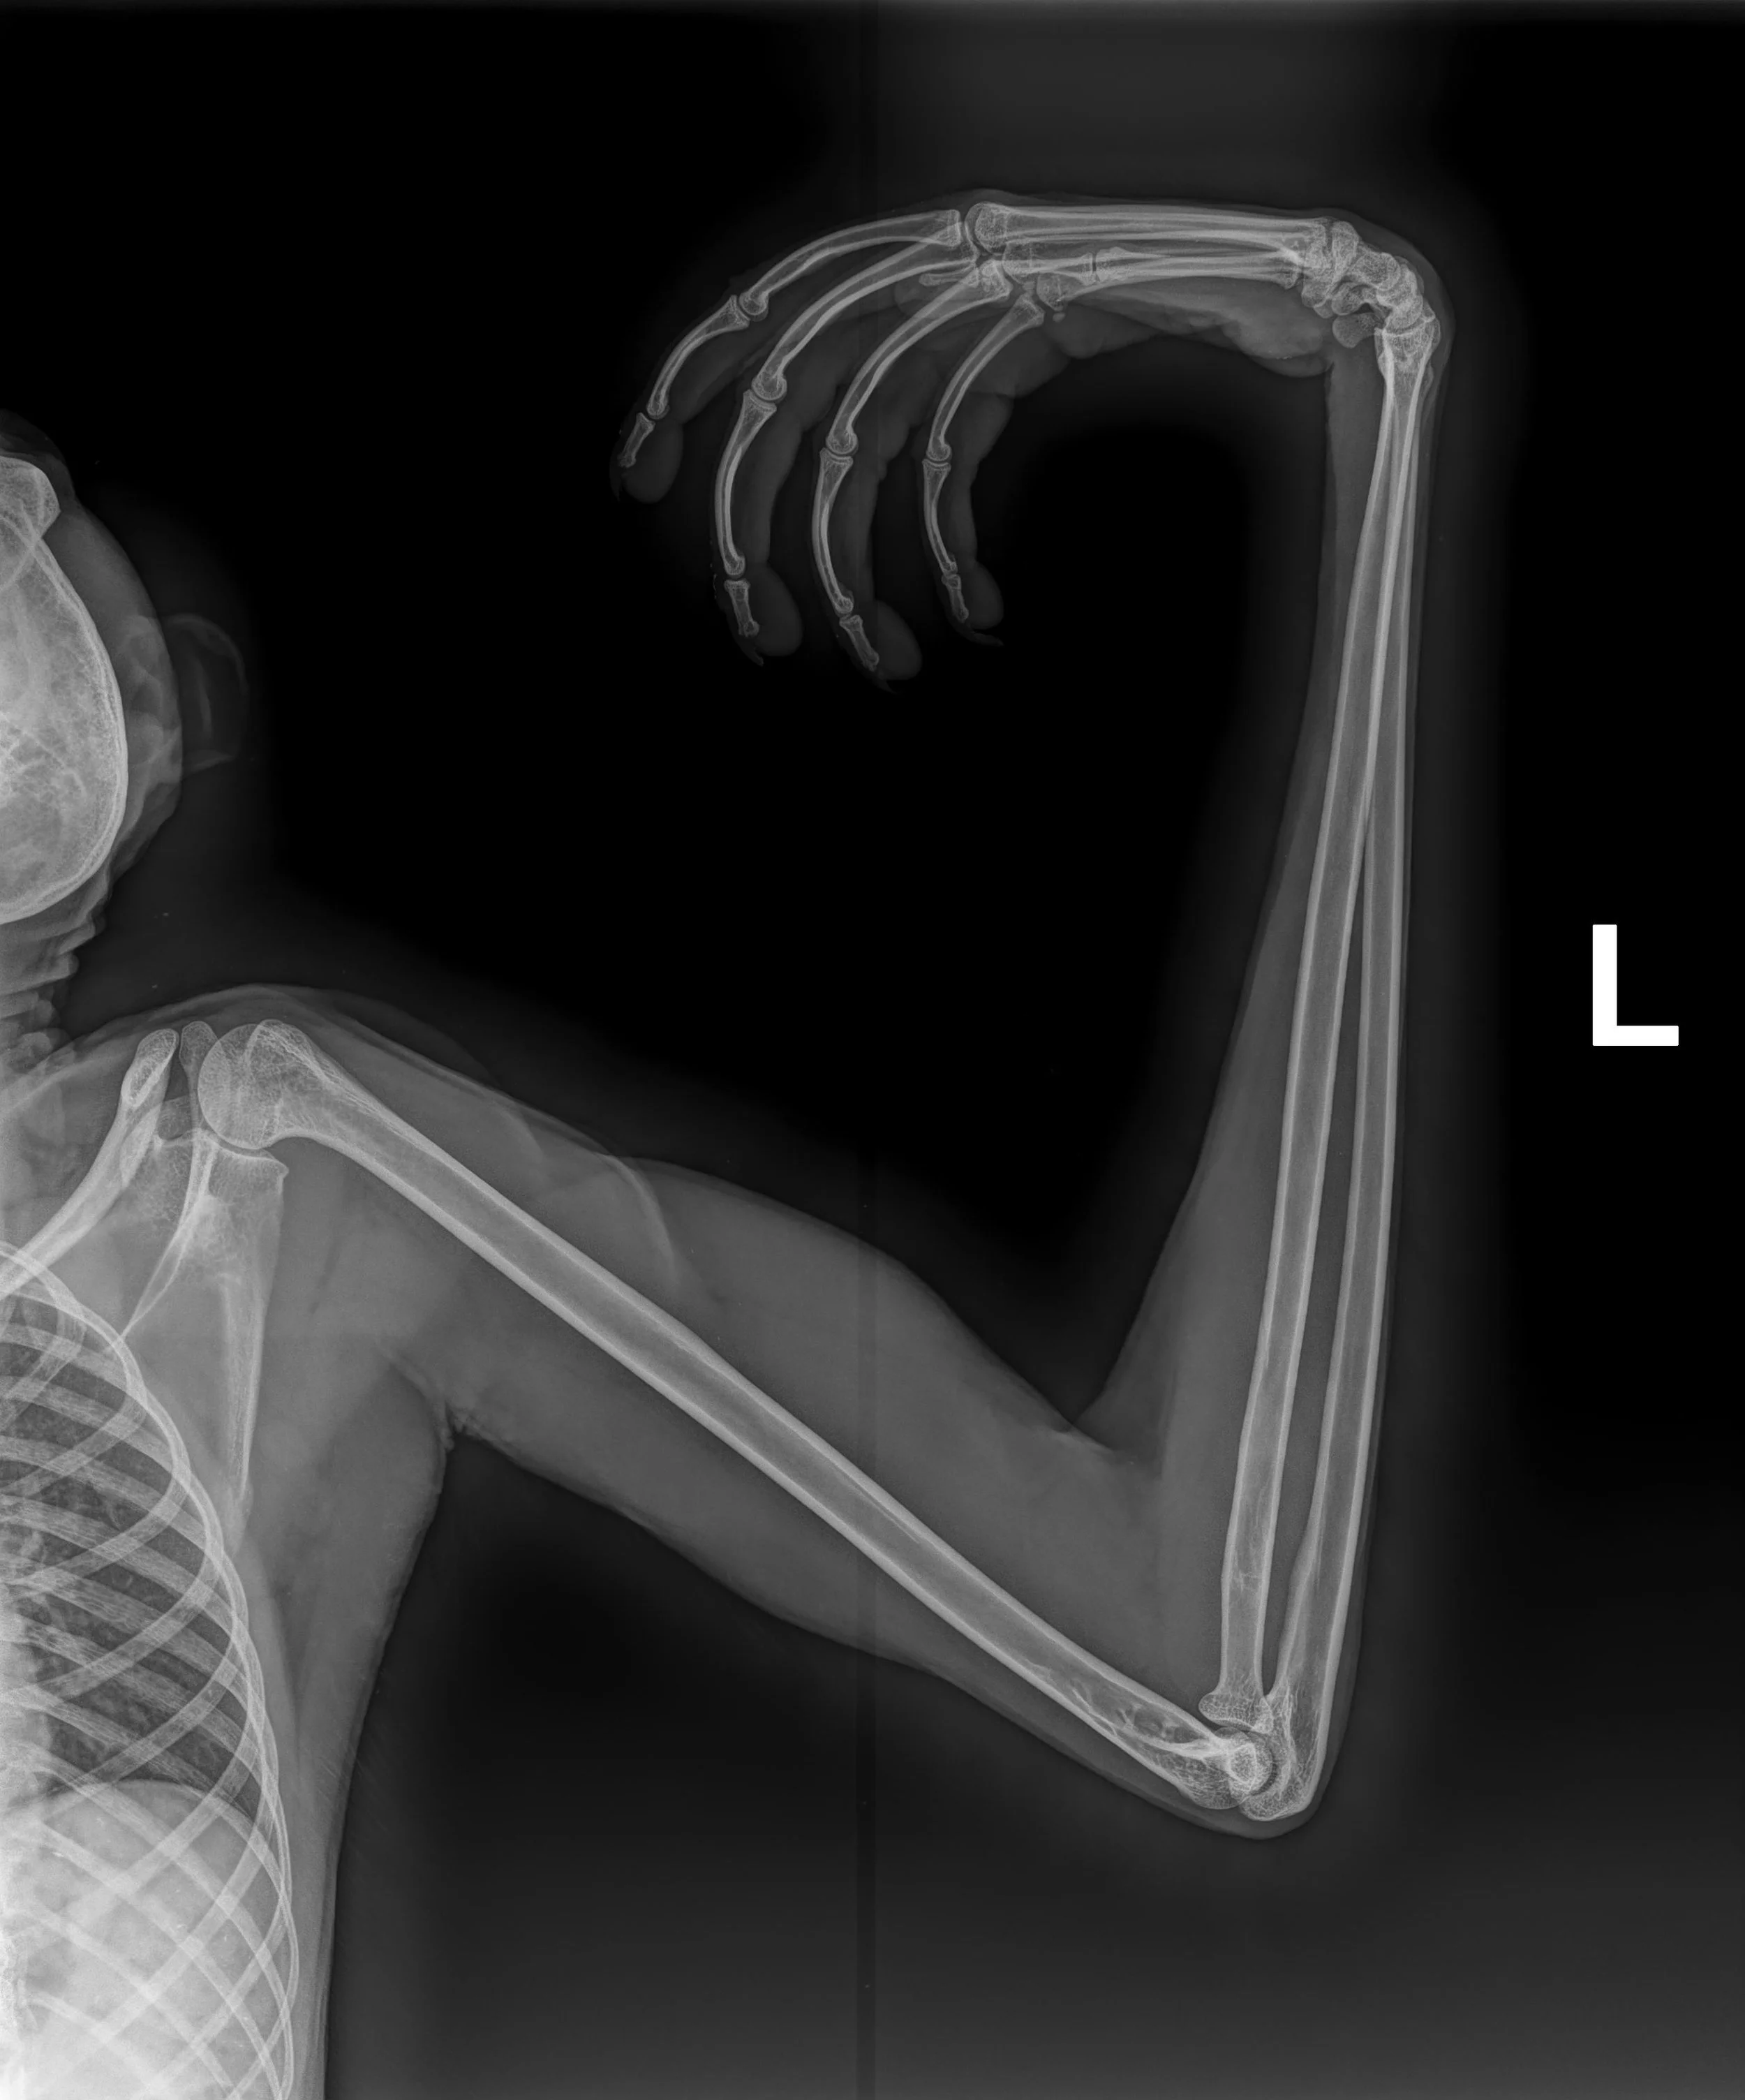

X-ray image of a left arm showing the bones, including the humerus, radius, and ulna, with a flexed elbow.